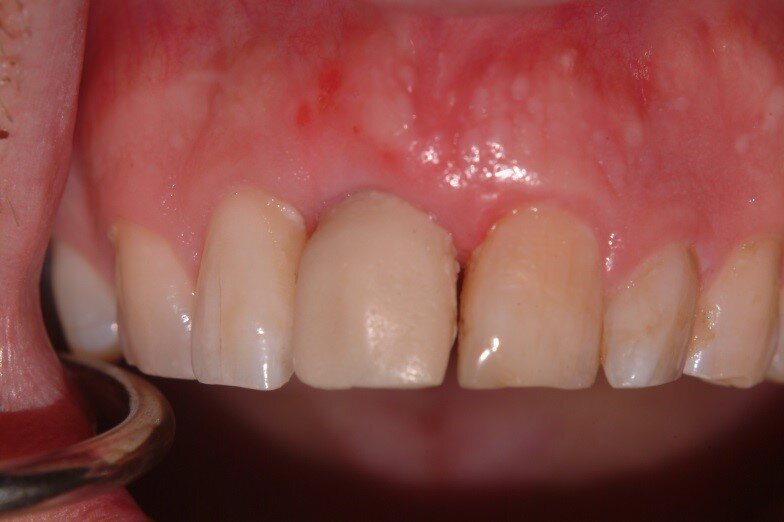

Patient RR was a healthy non-smoking 44 year old male who presented with a complaint of an unaesthetic upper right central incisor with extensive recession showing a large amount of darkened labial root surface. The situation was worsened by a high smile line and a porcelain crown contrasting dramatically with the root colour. He had had periodic swelling at the apical part of the recession over a long period. There was a history of trauma in his teens leading to root canal treatment and a crown, and subsequent apicectomy in his 20s. Clinical examination revealed an otherwise periodontally healthy, well looked-after mouth. (Fig. 1, 2, 3)